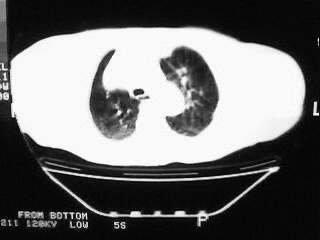

女,79,咳 嗽月余,无其它不适

1)两肺炎症。2)食管裂孔疝可能;建议行上消化道钡餐检查。